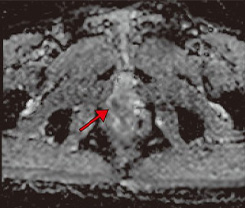

Aplio meによる臨床画像 症例:前立腺がんに対する経直腸エコーによる針生検

c:前立腺右葉辺縁領域にPI-RADS 4の病変を認める。 c:前立腺右葉辺縁領域にPI-RADS 4の病変を認める。

d:cと合致した部位にADCにてPI-RADS 4病変を認める。cの部位とbの画像でSMI陽性の病変は一致している。 d:cと合致した部位にADCにてPI-RADS 4病変を認める。

cの部位とbの画像でSMI陽性の病変は一致している。

abcd図

クリニックでは、通常の検査のほか前立腺針生検でもSMIを活用している。SMIは、モーションアーチファクトを除去するアルゴリズムを使用し、従来のカラードプラでは描出困難だった微細血管の低流速血流を高感度に描出できる。前立腺針生検は事前にMRI検査を行い、MR画像を参考に会陰部から針を挿入し組織を採取するが、SMIで前立腺がん特有の微細な血流の有無を確認しながら行うため、通常の前立腺針生検より高精度に検査が行える。宮嶋院長は、「MRI所見でPI-RADS(Prostate Imaging Reporting and DataSystem)スコアが4以上であれば、SMIで微小血管血流が検出できる印象です。実際に、SMIによりMRI所見と同様に血流が描出され、腫瘍を検出できた症例もあり、大変有用だと思います」と評価する。